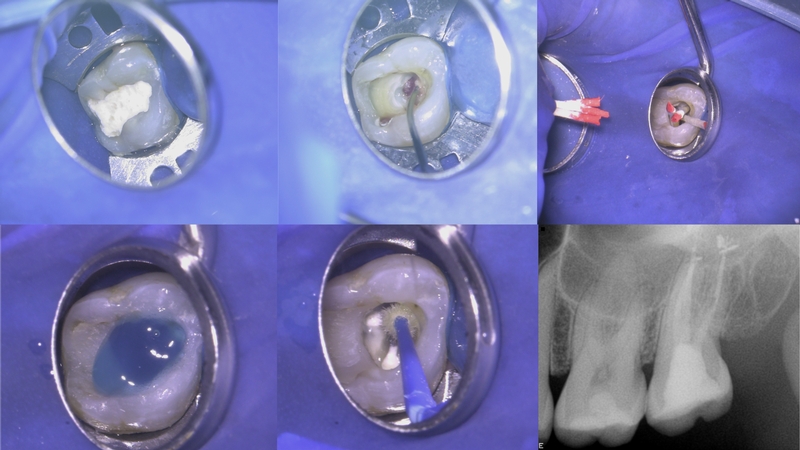

A endodontia é a especialidade da odontologia que apresenta  o maior índice de sucesso. Alcançado, evidentemente, através de um tratamento que envolve muito conhecimento, experiência e  disposição, além de,  seleção e qualidade do arsenal odontológico utilizado e o estabelecimento de um correto e preciso protocolo, o qual deverá ser seguido com muito rigor.  Através da evolução, passou a ser uma especialidade mais científica e previsível.

Há alguns anos a endodontia começou a mudar,  e de forma expressiva, porquanto da mudança de paradigmas em que se estabeleceu conceitos mais alicerçados em pesquisas clínicas e científicas. O princípio de que a endodontia deve cumprir o papel de: abrir, tratar e fechar, é um dos fundamentos básicos da terapia endodôntica. Entretanto existem vários fatores interferem de forma direta ou indireta.

O que é importante enfatizar?!  O entendimento, de qual é o objetivo primordial do profissional da endodontia: promover a limpeza e modelagem dos canais radiculares, conquistando o controle da infecção. E para que  esta meta se concretize, é imperativo o  conhecimento da anatomia para poder dominá-la. Pois a primeira intenção do endodontista que encontra a entrada do canal, é ir ao encontro do forame. Independente da técnica utilizada a negociação com a anatomia interna para encontrar o forame é um dos objetivos  primordiais para o sucesso da terapia endodôntica.

Após o encontro com o forame, “peça principal do xadrez”, se faz patência, se recua 1, 1,5, 2mm… se realiza batente ( stop ) apical, se amplia forame, é outro ponto a ser analisado. Vai depender da filosofia do profissional. Particularmente, nos últimos anos, venho realizando a Técnica da FOP-UNICAMP com patência e ampliação do forame apical com resultados surpreendentes.

Na endodontia muito se discute, muita discordância existe e muito se tem a aprender… entretanto existem conceitos que transpõem as discussões, pois independe de qual corrente seja, que é condição básica para a realização de uma endodontia de qualidade, como: isolamento absoluto ( respeito aos princípios básicos da terapia ), encontrar o forame apical ( para estabelecer o limite de trabalho ), ter o controle da infecção ( abrir, tratar, selar) e o selamento do espaço radicular e coronário.